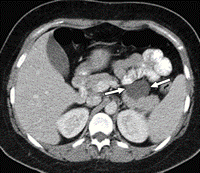

- Kontrastlı KT və ya MRT standart müayinədir, şişi və yayılma dərəcəsini müəyyənləşdirilməsində önəmlidir.

- Görüntüləmdə: erkən arterial fazada contrast tutan və venoz fazada yuyulan, MRT-də hipointens, ətraf toxumalara invaziv, böyüməyə meylli, baş nahiyyəsində yerləşərək xoledoxu və pankreatik axacağı genişləndirən (“iki axacaq simptomu”) törəmə

- Kontrastlı KT/MRT (5 mm-lik kəsiklərlə aparılan kontrastlı KT/MRT 50 – 60% həssaslıq göstərir.